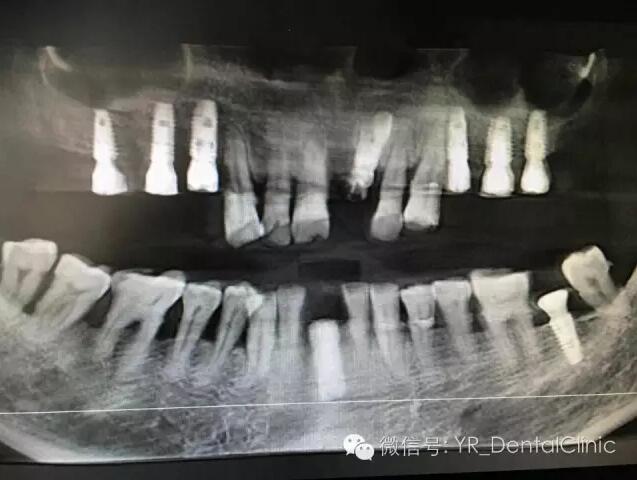

种植后全景片(3小时完成9颗种植牙正真体现了微创、快捷、术后无痛)广安市******例数字化种植